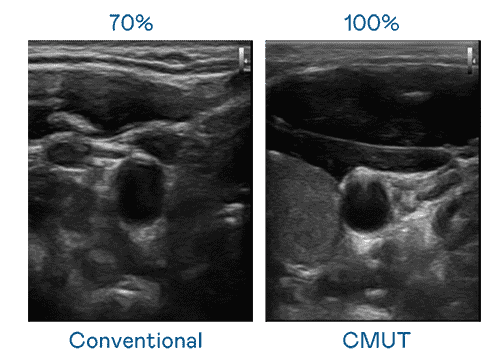

CMUT 技术是一种用电容式微机电元件来产生超音波讯号的技术。。。。与传统 PZT 压电式技术相比,,,CMUT 频宽增加 30%,,更宽频的超音波讯号让影像解析度大幅提升,,,,是实现高影像品质医疗超音波扫描、、、、促进精准医疗发展的关键技术。。。。

大频宽带来超清晰影像

超音波影像的解析度高低,,,,首先取决于探头能发出的讯号频宽。。人生就是博 CMUT 可提供高清晰的超音波讯号,,,,提供高频宽、、、高灵敏度、、影像纹理细节更高的超音波影像,,,协助医护人员缩短影像判读时间及利用精准的医疗影像进行诊断。。